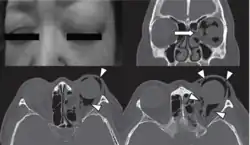

Woman with preorbital swelling in orbital emphysema shown in CT scans

Computed tomography is effective and sensitive in the diagnosis of orbital emphysema,[3][37] as it can confirm the anatomical location and size of air, bony defects, indentation of the eyeball, and the condition of the optic nerve, as well as the presence of any extraocular muscle entrapment and herniation of preorbital fat into the sinus cavities.[3][15][38] The location of the orbital emphysema is present near the site of the fracture.[1][3] The scans are usually taken along the transverse plane. Transverse images allow the evaluation of fractures in medial and lateral orbital walls. By reformatting these transverse images or taking coronal images, the examination of orbital floor and roof is permitted. Helical scanning is preferred as it has a lower imaging time and radiation dose comparing to conventional scanning, especially when reforming transverse helical scans into coronal images.[3] The staging of orbital emphysema can then be determined with visual acuity examination and ophthalmoscopy.[6] A disadvantage of using a CT scan is that when detecting air after orbital trauma, the presence of a wooden foreign object can give a false positive result of orbital emphysema. The wooden object can mimic the presence of orbital emphysema. Therefore, patients’ medical history is crucial in making the correct diagnosis.[3]